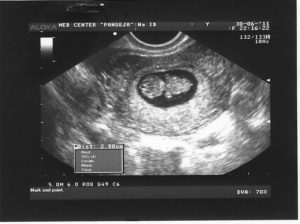

На протяжении беременности каждая женщина должна пройти три плановых УЗИ. Срок проведения плановых исследований:

• первое УЗИ назначается на срок от 10 до 12 недель;

• второе УЗИ проводят, когда срок беременности составит от 18 до 22 недель;

• третье УЗИ нужно будет пройти ближе к родам, когда срок составит от 33 до 35 недель.

Помимо плановых УЗИ могут быть назначены и дополнительные, если появятся показания.

Совет! Проведение УЗИ не оказывает отрицательного влияния на плод, поэтому будущие мамы не должны бояться, если врач рекомендует пройти дополнительное обследование.

Стоит ли делать УЗИ на 9 неделе? Ведь первое плановое обследование назначают не ранее 10 недели? Ответить на эти вопросы сможет только врач. Возможно, он перенесет УЗИ на неделю, когда срок беременности достигнет 10 недель. А может быть порекомендует не ждать 10 недели, а пройти обследование немедленно. Как правило, УЗИ ранее 10 недели назначают:

• при подозрении на внематочную беременность;

• для подтверждения или исключения многоплодной беременности;

• для выявления патологий плода, плаценты, матки;

• подозрение на то, что беременность перестала развиваться.

Если же особых показаний нет, то врач, как правило, рекомендует дождаться 10 недели и пройти плановое исследование. Но даже в том случае, если врач не советует ждать наступления 10 недели, будущая мать не должна пугаться.

Внеплановое исследование вполне может подтвердить, что с плод развивается нормально. То есть, оно нужно еще и для того, чтобы будущая мама перестала волноваться. Ведь нервозность матери отрицательно влияет на развитие плода.